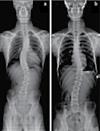

38 콜로라도 타임즈 · 2023년 5월 11일 목요일 · 1076호 교통사고 후유증 / 목 통증 / 목 디스크 / 오십견 / 어깨통증 말초신경장애: 손, 발, 다리의 통증, 저림, 근육약화감, 감각상실 (편)두통 / 불면증 / 어지러움 / 턱관절 장애(TMJ) 척추측만증(Scoliosis) / 척추협착증 / 허리수술 후유증 허리통증 / 허리 디스크 / 관절염 / 좌골신경통 / 고관절, 발목, 손목 통증 ▪ ▪ ▪ ▪ ▪ ▪ ▪ ▪ ▪ 최첨단 목/허리 디스트 치료기기 최신형 디지털 X-ray 시설 Therapeutic Massage ▪초음파, 전기치료 Gonstead Chiropractic 교정치료 치료 진료과목 교통사고 치료 전문 자동차 보험 건강 보험 상해 보험 Southern California University of Health Science Doctor of Chiropractic 콜로라도주 척추신경 보드 정회원 캘리포니아주 척추신경과 보드 정회원 National Board 척추신경과 정회원 손석기 D.C. 원장, 척추신경 전문의 chiro1health@gmail.com Open Hours 월/수/금 9am-6pm 화/목: 2pm-6pm 청소년을 위한 척추교정 프로그램